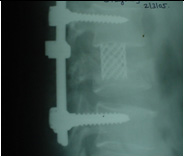

DISC SURGERY LYSTHESIS CORRECTION

SPINAL TRAUMA & DEFORMITY CORRECTION